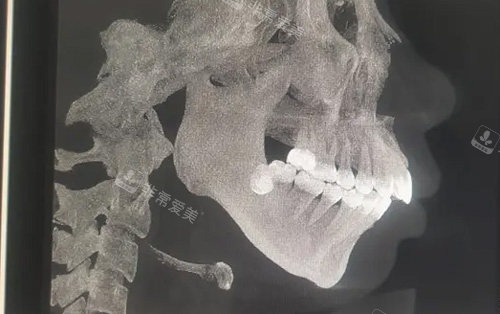

需要做正颌手术的骨骼图

不同于传统正颌手术的经验化操作,朴正国引入CT三维重建与动态咬合模拟系统,术前通过数智化建模精又准计算颌骨移动轨迹,将手术误差控制在0.1毫米内。

借助3D打印定制导板,截骨路径可提前规划,避免术中盲目操作,让颌骨调整既符合生理结构,又能契合患者面部美学比例,实现“量体裁衣”式的个性化手术方案。